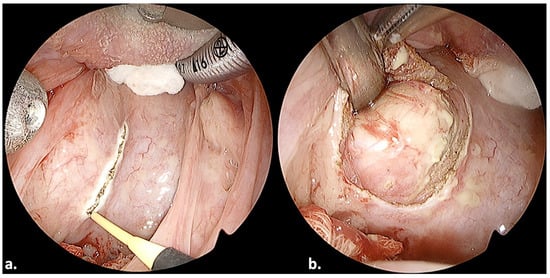

3.5. Case 12

3.6. Case 13